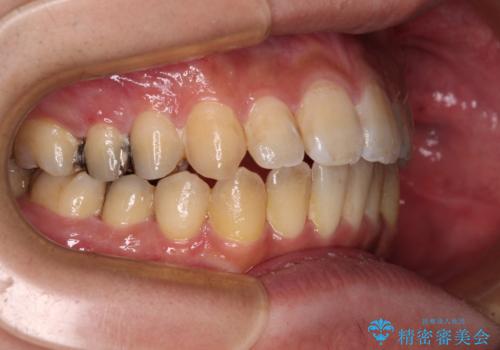

オープンバイトと目立つ銀歯 インビザライン矯正とセラミック修復治療

- 奥歯の目立つ銀歯と上下前歯の叢生と隙間を気にして来院された患者様です。

開咬の治療は、前歯を閉じるように動かすとともに、上下臼歯を圧下(骨内にめり込ませる)させることで進めて行きます。

インビザラインは臼歯の圧下を効果的に行えるため、インビザラインを用いて矯正治療を行うこととしました。

銀歯については、矯正治療により咬合関係を改善し、矯正治療後半に修復治療を行うこととしました。